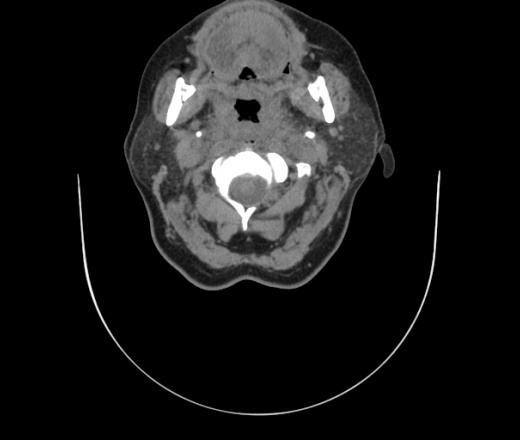

Женщина поступила в х/о спустя 4 дня после того как при употреблении карася подавилась костью.

Наличие газа в средостении на протяжении тел С2-С6 (медиастинальна эмфизема); рыбная кость на уровне тела С6.

При всем уважении, но говорить о медиастинальной эмфиземе, оценивая мягкие ткани шеи, как-то слишком резко. На мой взгляд, это ретрофарингеальное пространство.

Эвакуировали почти 100мл гноя. Но кость не смогли найти. Думаю что она даст дальнейшее ослоднение. Эндоскопически за черпалонадгортаной звязкой не смогли зайти в пищевод, все мягкие ткани отечные, просвет пищевода сдавлен. По всей видимости параэзофагеальная клетчака тоже задействована. Эмпиема, если ее можно так назвать, незнаю как правильно дошла до уровня яремной вырезки. Чем закончиться напишу. Ждем медиастинита.

Флегмона заглоточного пространства шеи, только операция, флегмоны вскрывают. Риск медиастинита.

Согласен с Вами; конечно, наличие газа в клетчатке ретрофарингеального пространства (затмение с опечаткой..). К сожалению, процесс "продвигается" к медиастиниту. Но почему никто, не отмечает наличие рыб. кости; или это для Всех очевидно?

Так вы уже отметили. Хотя ориентировал бы не скелетотопически, а на перстнечерпаловидный сустав.

Кость то мы сразу выявили, размеры где то 17*2мм, но ее так и не получается найти в этой каше